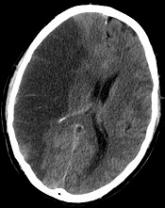

Credit: Lucien Monfils Researchers say they’ve developed a technique that can predict—with 95% accuracy—which stroke patients will benefit from...